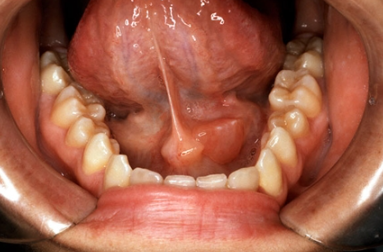

침샘염은 귀 밑 이하선이나 턱 밑 악하선에 염증이 생기는 질환으로, 붓기와 통증, 침 분비 감소, 발열 등 다양한 증상이 동반될 수 있습니다. 특히 중장년층에서 침 분비가 줄면서 발생 빈도가 높아지며, 증상에 따라 초기 자가관리가 가능하나 일정 수준 이상이면 병원 진료가 권장됩니다. 이 글은 의료적 조언이 아닌 일반적인 건강 정보 제공 목적으로 구성되었으며, 실제 진단과 치료는 전문가의 판단을 따르시길 바랍니다.

1. 침샘염 주요 증상

아래는 침샘염이 의심될 수 있는 대표적인 증상들입니다. 특히 다음 증상이 1~2일 이상 지속되거나 점점 악화된다면 병원 방문을 고려해보세요.

- 귀 밑(이하선) 또는 턱 밑(악하선)에 단단하고 아프게 붓는 부종

- 식사 시 침샘 부위 통증이 갑자기 심해지는 식사통증

- 입안에서 고름이 나오거나 불쾌한 냄새/맛이 느껴짐